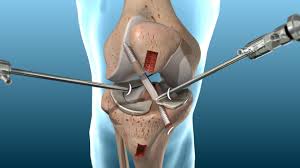

Arthroscopy is a minimally invasive procedure used to diagnose and treat joint problems, especially in the knee, shoulder, ankle, and wrist. A small camera called an arthroscope is inserted through a tiny incision, allowing the surgeon to see inside the joint. Other small tools are used to repair damage like torn cartilage or ligaments. It causes less pain and scarring compared to open surgery and allows for quicker recovery. Most arthroscopies are outpatient procedures, helping patients return to normal activities faster.

ACL reconstruction is a surgical procedure used to repair a torn anterior cruciate ligament (ACL) in the knee. The ACL is vital for stabilizing the knee during activities like running or jumping. In this surgery, the torn ligament is replaced with a graft, often taken from the patient’s own tendon or a donor. The procedure helps restore knee stability, improve mobility, and reduce pain. ACL reconstruction is typically followed by rehabilitation to strengthen the knee and return to normal activities.